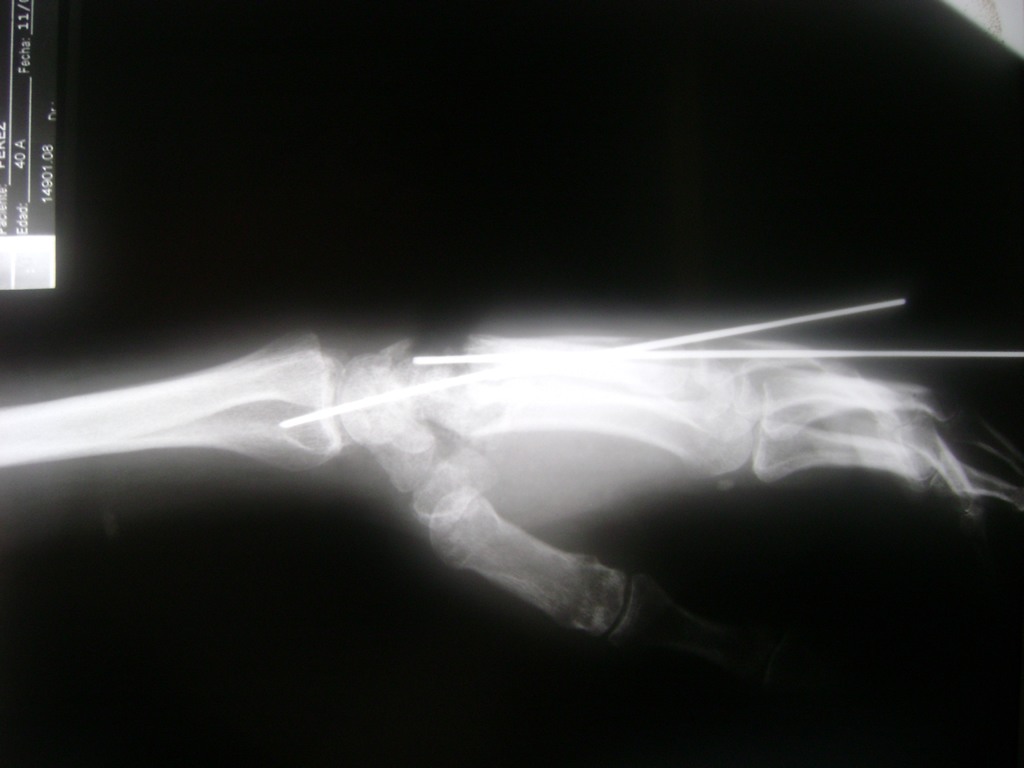

Cirugías de Codos - Cirugías de Muñecas y Manos

Los procedimientos más comunes en cirugía de la mano son aquellos destinados a reparar traumatismos, incluyendo lesiones de tendones, nervios, vasos sanguíneos, y articulaciones; huesos fracturados; y quemaduras, cortes, y otros daños de la piel.